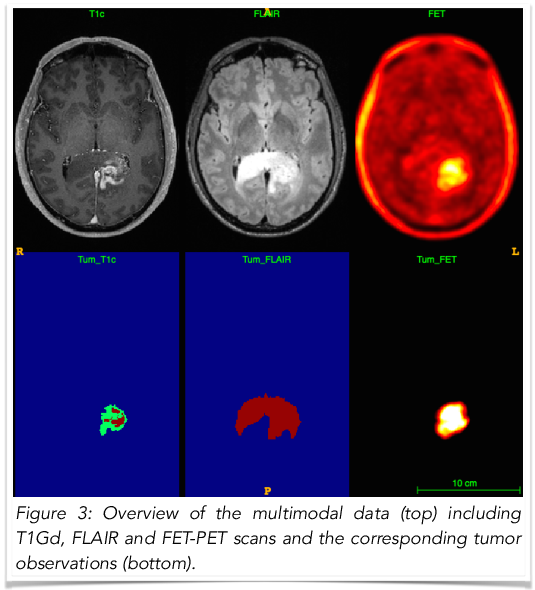

This example shows how to calibrate the tumor growth model with respect to patient medical scans to obtain patient-specific predictions about the tumor cell density, which could be used for the radiotherapy planning (as presented in [Lipkova 2018] in References). The used medical data include structural MRI (T1Gd, FLAIR) and functional FET-PET scans. The inference procedure is automated and its usage is explained in the following subsections.

Figure 3 shows an overview of the input modalities and tumor observations. The test data for this tutorial can be obtained here and the set-up scripts are provided in GliomaSolver/Simulations/PatientInference/.